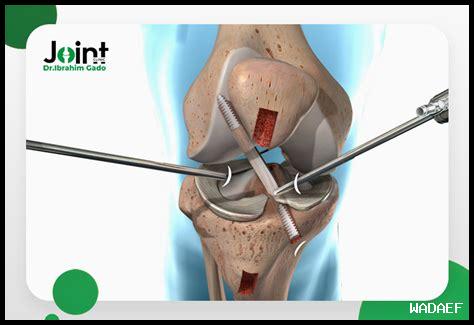

غضروف الرباط الصليبي هو جزء مهم من الجهاز العضلي الهيكلي للإنسان. يقع في الركبة ويعتبر أحد الأجزاء الرئيسية التي تساعد في تثبيت الركبة وتحمل الضغط عليها. يتكون غضروف الرباط الصليبي من نسيج ضام يشبه الليف ويتمتع بمرونة عالية.

تتمثل وظيفة غضروف الرباط الصليبي في تثبيت الركبة ومنعها من الانزلاق أو التحرك بشكل غير طبيعي. يعمل الرباط الصليبي مع الأربطة الأخرى في الركبة لضمان استقرارها وحمايتها من الإصابات.

. بالإضافة إلى ذلك، يساعد غضروف الرباط الصليبي في توجيه حركة الركبة وضمان سلامتها أثناء الحركة.

يمكن أن يتعرض غضروف الرباط الصليبي للتلف نتيجة للإصابات الرياضية أو الحوادث الشديدة. قد يحدث تمزق في الرباط الصليبي نتيجة لانحناء الركبة بشكل غير طبيعي أو تعرضها لضغط شديد. كما يمكن أن يتلف غضروف الرباط الصليبي نتيجة للشيخوخة وتقدم العمر.

يعتمد علاج تلف غضروف الرباط الصليبي على درجة الإصابة وحجم التلف. قد يتطلب العلاج الحفاظي استخدام العلاج الطبيعي والتمارين الرياضية لتقوية العضلات المحيطة بالركبة. في حالات التمزق الشديد، قد يتطلب الأمر إجراء عملية جراحية لإصلاح غضروف الرباط الصليبي.